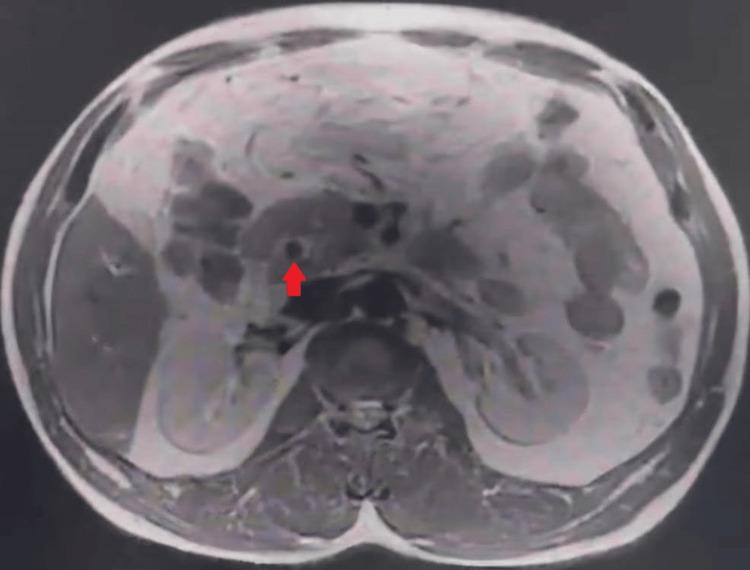

A contracted or "vanishing" gallbladder is a condition characterized by severe atrophy or fibrosis of the gallbladder, often resulting from chronic inflammation, recurrent cholecystitis, gallstone disease, or metabolic disorders such as diabetes and chronic alcohol use. The etiopathogenesis involves progressive fibrosis due to persistent biliary obstruction, chronic infection, or impaired blood flow, particularly in patients with liver cirrhosis. While the exact incidence remains unclear, it is more prevalent in individuals with long-standing hepatobiliary diseases or metabolic syndromes. Common symptoms include severe right upper quadrant pain, jaundice, nausea, vomiting, and signs of obstructive jaundice, such as dark urine and pale stools. Diagnostic investigations typically involve ultrasound, contrast-enhanced computed tomography (CECT), magnetic resonance cholangiopancreatography (MRCP), and endoscopic retrograde cholangiopancreatography (ERCP) to assess biliary obstruction, liver pathology, and gallbladder morphology. Treatment requires a multidisciplinary approach, including initial ERCP for biliary decompression, followed by surgical intervention (laparoscopic or open cholecystectomy), with conversion to open surgery often necessary due to dense adhesions and fibrosis. Postoperative care focuses on managing comorbidities, preventing complications, and long-term monitoring of liver health. This case report presents the challenging management of a 34-year-old male with a history of diabetes mellitus, chronic alcohol use, and liver cirrhosis, who presented with severe right upper quadrant pain, jaundice, and ascites. Initial evaluation revealed cholangitis, calculous cholecystitis with choledocholithiasis, and imaging findings consistent with liver cirrhosis. The patient underwent ERCP for biliary stenting and sludge extraction, followed by an attempted laparoscopic cholecystectomy. Intraoperatively, dense adhesions and fibrosis obscured the gallbladder, confirming a contracted or "vanishing" gallbladder, prompting conversion to an open procedure. The case highlights the diagnostic complexities of contracted gallbladders, which often result from chronic inflammation, fibrosis, or metabolic disorders. Preoperative imaging, including ultrasound and MRCP, played a critical role in identifying biliary obstruction and liver pathology. However, intraoperative findings necessitated adaptive surgical decision-making to mitigate risks such as bile duct injury or hemorrhage. The patient's multiple comorbidities further complicated management, emphasizing the need for a multidisciplinary approach involving gastroenterologists, surgeons, and hepatologists. Postoperative recovery was closely monitored for complications, including infection and bile leaks. The patient was discharged with follow-up care focusing on liver health, diabetes management, and alcohol cessation. This report underscores the importance of thorough preoperative assessment, flexibility in surgical technique, and collaborative care in optimizing outcomes for patients with complex gallbladder pathology. Future research should explore long-term outcomes and improved imaging techniques to enhance surgical planning for such challenging cases.

胆囊萎缩或“消失”是一种以胆囊严重萎缩或纤维化为特征的病症,通常由慢性炎症、复发性胆囊炎、胆结石病或代谢紊乱(如糖尿病和长期酗酒)引起。其发病机制涉及由于持续性胆管梗阻、慢性感染或血流受损导致的进行性纤维化,在肝硬化患者中尤为常见。虽然确切发病率尚不清楚,但在患有长期肝胆疾病或代谢综合征的个体中更为普遍。常见症状包括右上腹剧痛、黄疸、恶心、呕吐以及梗阻性黄疸的体征,如尿色深和大便色浅。诊断性检查通常包括超声、增强计算机断层扫描(CECT)、磁共振胆胰管造影(MRCP)和内镜逆行胆胰管造影(ERCP),以评估胆管梗阻、肝脏病理和胆囊形态。治疗需要多学科方法,包括首先进行ERCP以解除胆管梗阻,随后进行手术干预(腹腔镜或开腹胆囊切除术),由于致密粘连和纤维化,通常需要转为开腹手术。术后护理重点在于管理合并症、预防并发症以及对肝脏健康进行长期监测。本病例报告介绍了一名34岁男性患者的具有挑战性的治疗过程,该患者有糖尿病、长期酗酒和肝硬化病史,出现右上腹剧痛、黄疸和腹水。初步评估显示胆管炎、结石性胆囊炎伴胆总管结石,影像学检查结果与肝硬化相符。患者接受了ERCP胆管支架置入和胆泥清除,随后尝试进行腹腔镜胆囊切除术。术中,致密粘连和纤维化使胆囊难以辨认,证实为萎缩或“消失”的胆囊,促使手术转为开腹手术。该病例突出了萎缩性胆囊的诊断复杂性,这通常由慢性炎症、纤维化或代谢紊乱引起。术前影像学检查,包括超声和MRCP,在识别胆管梗阻和肝脏病理方面发挥了关键作用。然而,术中发现需要灵活的手术决策以降低胆管损伤或出血等风险。患者的多种合并症使治疗更加复杂,强调了需要胃肠病学家、外科医生和肝病学家参与的多学科方法。术后密切监测恢复情况以预防并发症,包括感染和胆漏。患者出院时接受以肝脏健康、糖尿病管理和戒酒为重点的随访护理。本报告强调了全面术前评估、手术技术灵活性以及协作护理对于优化复杂胆囊病理患者治疗效果的重要性。未来研究应探索长期预后以及改进成像技术,以加强对此类具有挑战性病例的手术规划。